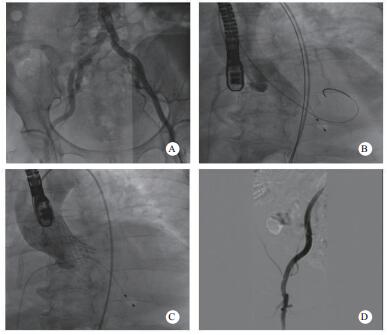

术后随访:患者术后病情稳定,病房继续住院3 d后顺利出院。术后1个月随访化验提示“proBNP 5 869 pg/mL,血肌酐185 μmol/L,肌钙蛋白T 0.118 ng/mL”,复查心超提示“LVEDD 5.19 cm,simpson's测得LVEF 58.6%;主动脉瓣口最大流速2.35 m/s,最大压差22 mmHg,平均压差10 mmHg,瓣口面积1.65 cm2”(图 4)。

| 图 4 患者术后1月随访超声心动图 |